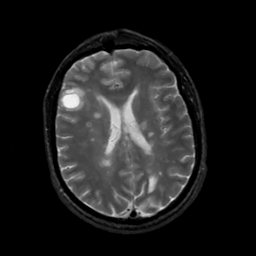

MR Study #5, March 10, 1991 -- Slice #32